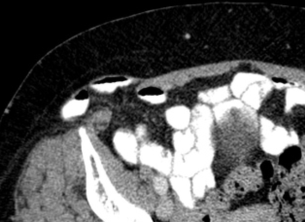

Filet au CT